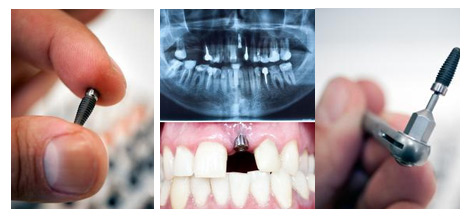

西安雁塔海涛口腔医院医生介绍说,单颗牙齿缺失优选种植牙修复,种植牙类似真牙原理,以手术方法在口腔牙槽骨组织中植入人工牙根(种植体)作为支持,并在人工牙根上进行牙冠修复的一种缺牙修复方法。因为种植牙可以获得与天然牙功能、结构以及美观度一样的修复效果。

一、修复时间短:拔牙后即刻种植,与传统种植牙修复相比,可大幅缩短顾客拔牙后的等待时间医学。

二、咀嚼功能强:与真牙的力学原理相似,能很好地恢复牙齿功能,咀嚼功能大大优于其他传统假牙。

三、稳固性好,舒适方便:人工牙根牙槽骨紧密结合,像真牙一样扎根在口腔里,具有很强的固位力与稳定性。由于不使用传统镶牙的卡环或牙套,因此,顾客口腔没有异物感,非常舒适、方便,而且有利于保持口腔的清洁卫生。